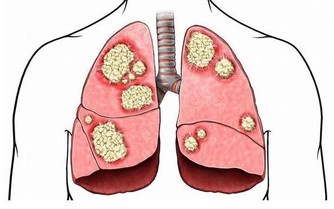

三、維生素C

維生素C抗氧化效果明顯,有利於促進人體新陳代謝速度,抑制黑色素形成,幫助皮膚變得白皙。維生素C在治療敗血症方面還有重要作用。

如果人體缺乏維生素C,就會對健康帶來嚴重影響,包括敗血症、牙周出血、蛀牙、多汗、軟骨病等。